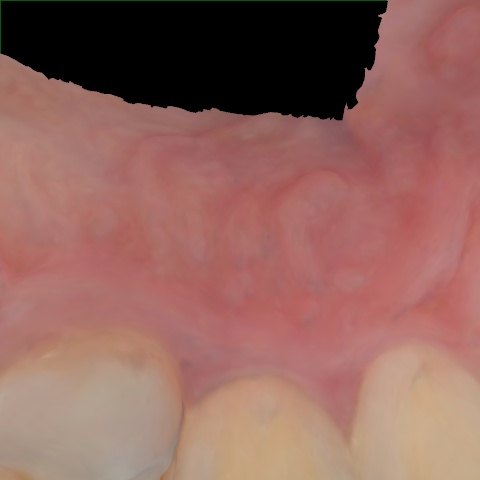

Annotated as "Good"